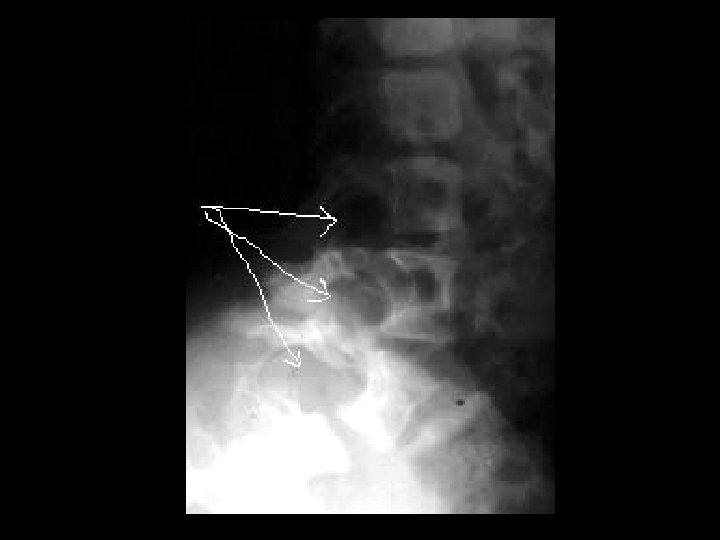

Fibrous dysplasia • Findings: – Mixed sclerotic and lytic lesion of the left hemipelvis and proximal femur – “shepherd's crook sign” • ddx: – NONE! – This is an Aunt Minnie!